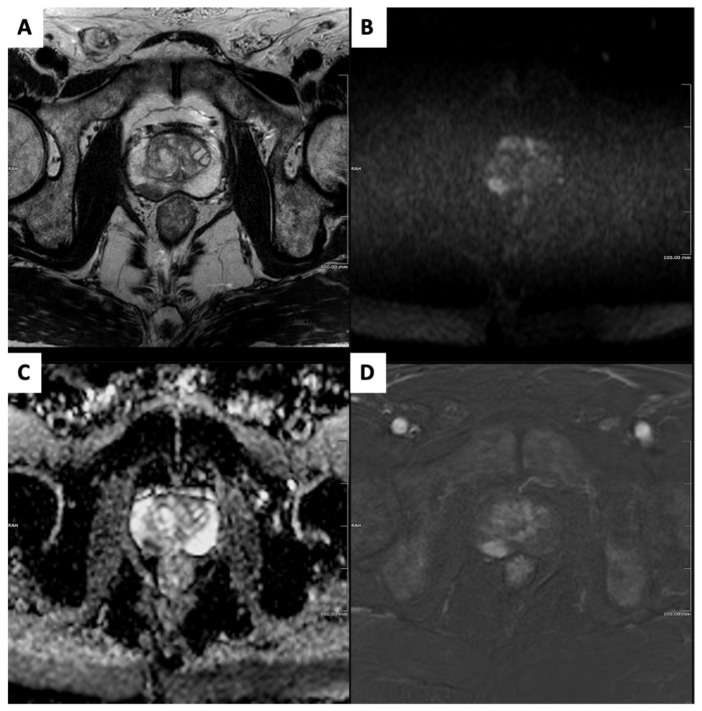

Figure 1.

Clinically significant prostate cancer in a 75-year-old biopsy-naïve subject who underwent magnetic resonance imaging (MRI) for raised prostatic-specific antigen level (7 ng/mL) and suspicious digital rectal examination. Prostate MRI showed a 13 mm PI-RADSv2.1 category 4 focus in the right mid-gland peripheral zone, demonstrating homogeneous moderate hypointensity on axial T2-weighted image (A); focal-restricted diffusion with marked hyperintensity on the high b-value image (B) and marked hypointensity on the apparent diffusion coefficient map (C); and focal, early enhancement on a digitally subtracted, fat-saturated T1-weighted image from the dynamic contrast-enhanced sequence (D). Targeted cores from transperineal biopsy showed a ISUP grade 2 prostate cancer.